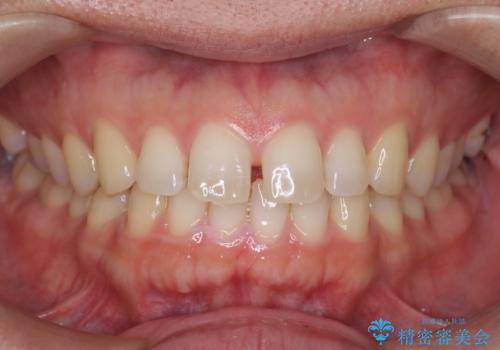

- 歯のがたつきを主訴に来院。

左右とも奥歯のがたつきがあり、左奥はすれ違っていました。

また、右奥は反対咬合になっていました。

インビザライン治療は主に奥歯のかみ合わせが大きな問題がない場合は特に問題なく終了しますが、今回のケースのように奥歯のかみ合わせが悪い場合、しっかり治らないことがあります。

患者様が気づかない範囲で妥協して終わるということをせず、しっかり奥歯に部分矯正を用いて大きな問題を解決してからインビザライン治療に入りました。

下の前歯を一本抜歯しています。(抜歯の本数は最小限にしています。)